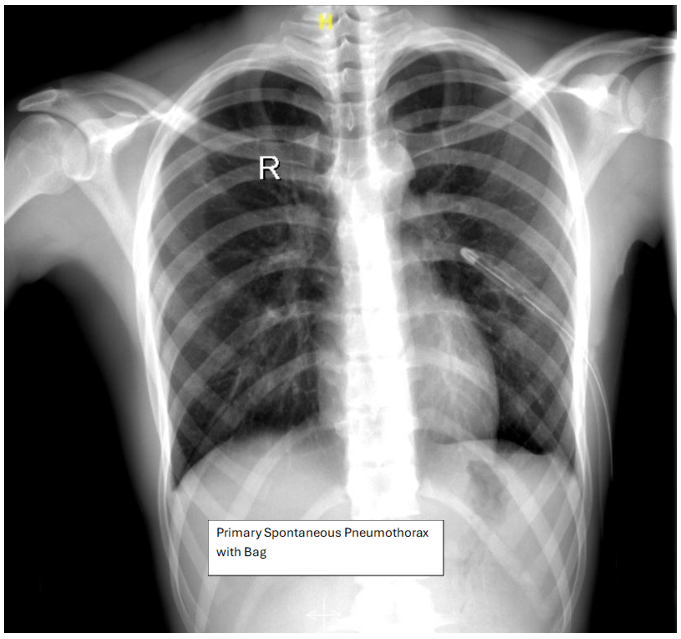

• The Heimlich valve group was used primarily for younger patients with primary or recurrent spontaneous pneumothorax, often reluctant to undergo surgery.

Figure 5